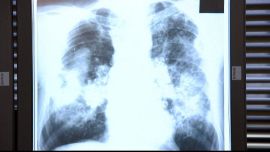

Black lung disease, a sometimes deadly respiratory illness that afflicts coal miners, is on the rise again in the US.